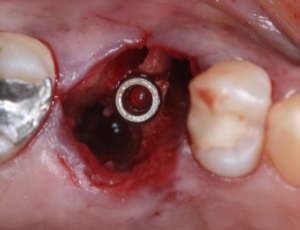

Vista oclusal do implante due-cone instalado na região doelemento16.